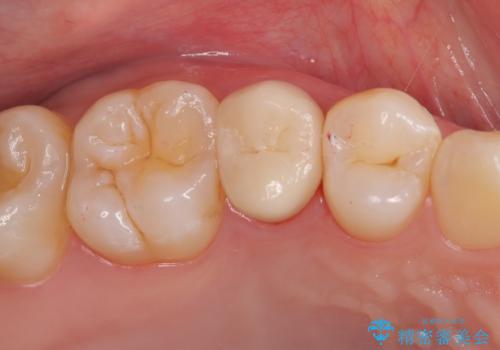

銀歯の下に虫歯 〈オールセラミッククラウン〉

担当医 瀧村怜未